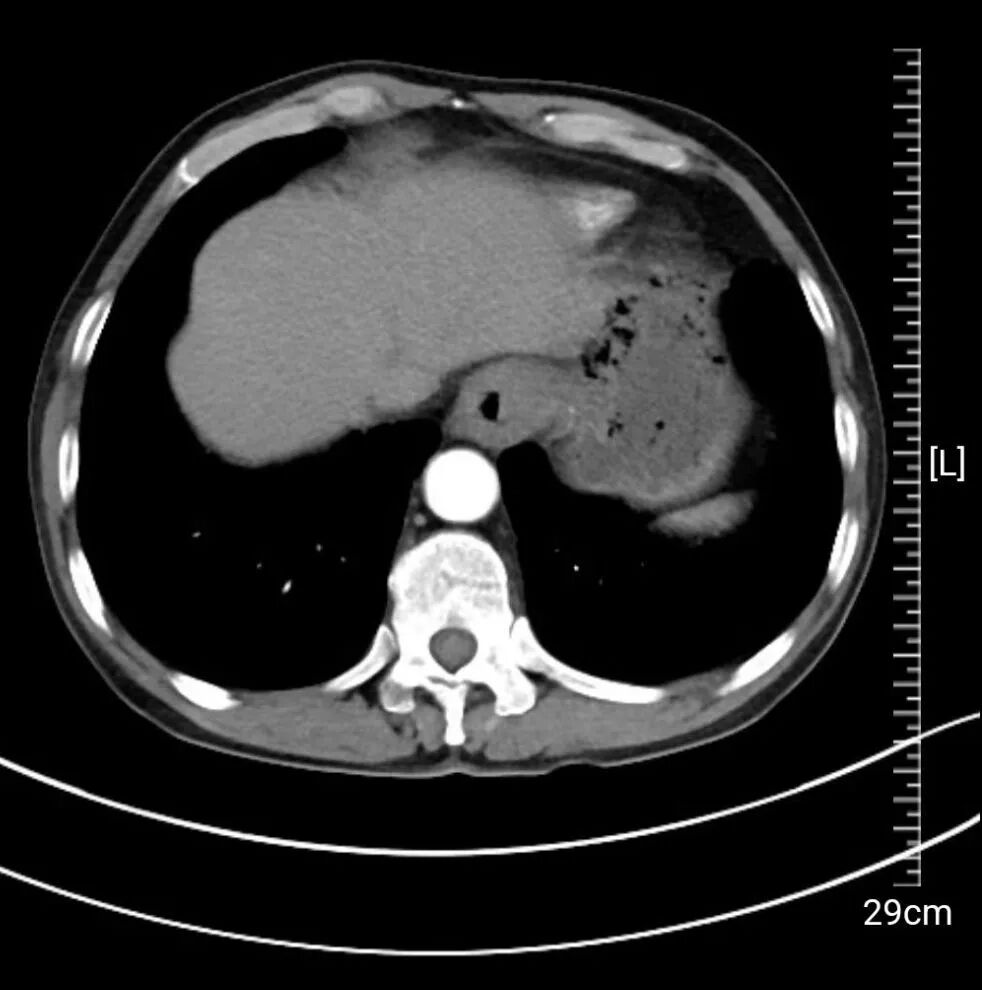

引言 / / Introduction 一口馒头,竟成了生命难以逾越的“大山”。过去一个多月,陈大爷(化名)仿佛置身于一场醒不来的噩梦——吞咽困难、胸骨疼痛,连半流食都吃得勉强。而今,在葫芦岛市第二人民医院胸外科,这场噩梦终于被孙振教授团队精湛的医术画上了句号。 PART. 01 吞咽困难查出食管癌 辗转求医找到“家门口的希望” PART. 02 高难度手术顺利切除 术后第三天即可下床 PART. 03 深耕胸外领域 以技术实力守护患者“生命通道” PART. 04 人民医院 人民名医